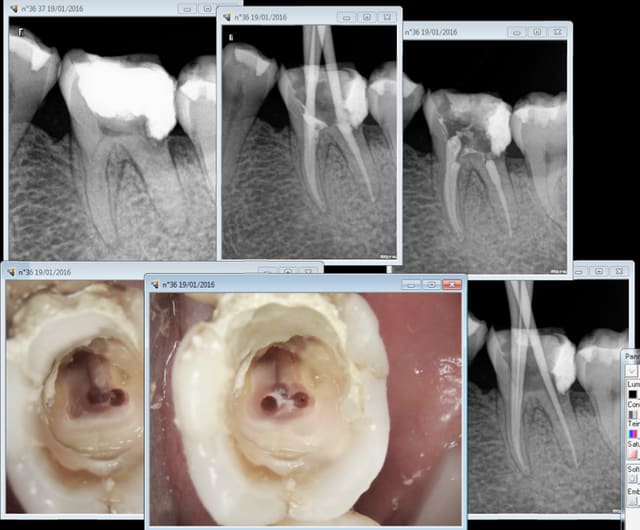

19/01/2016 à 23h48

Pas serein sur ce coup là mais il faut se méfier des apparences. Toutefois en cathéthérisme manuel j'aurais pu m'accrocher. Balles neuves quand même. -)))

pas de digue rhoooo le vilain ! -)))

Par contre chaud la limite en distal !

Un beau collage, no post no crown ... :D